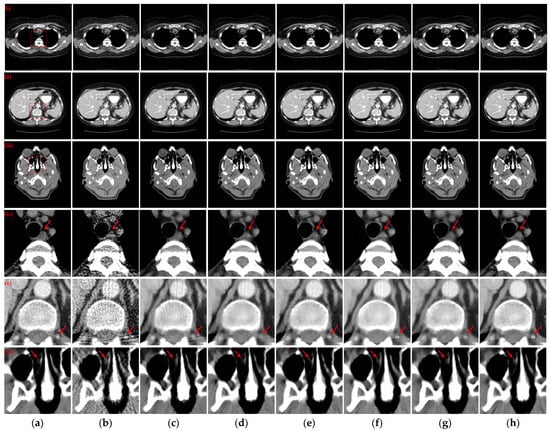

3.4. Robustness of Noise